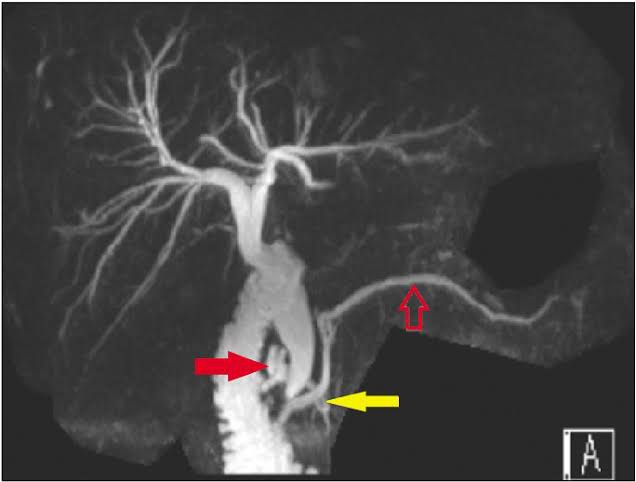

Magnetic resonance cholangiopancreatography or MRCP uses a powerful magnetic field, radio waves and a computer to evaluate the liver, gallbladder, bile ducts, pancreas and pancreatic duct for disease. It is noninvasive and does not use ionizing radiation.